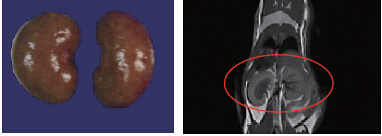

A 44.8 g mouse: kidney volume measured by MRI was 0.315 cm³; anatomical reference (water displacement method) measured 0.293 cm³. Imaging time: 10 minutes.